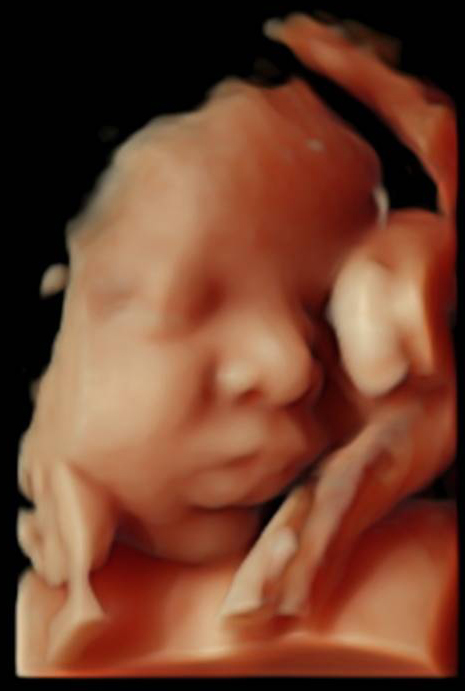

La ecografía 5 D en el embarazo, también conocida como ecografía emocional, resulta muy espectacular. Cuando te la hagas, verás a tu bebé en cuatro dimensiones antes de nacer, mientras está dentro de tu útero con una calidad de imagen muy realista. Podrás comprobar cómo se mueve, si hace gestos o incluso a quién de los dos se parece, a papi o a mami. Y, por supuesto, si es un niño o una niña.

La ecografía 4D ya supuso un importante avance en las pruebas de ultrasonidos. La ecografía 5D es una versión mejorada con imágenes que permiten ver la textura y el color de la piel. "La ecografía 4D introducía el factor tiempo y la paciente podía ver cómo se movía su bebé en ese momento”, explica Dra. Rocío Vellido Cotelo. Con las ecografías en 5D se cambia el color: la imagen en tono sepia característico de las ecografías en 4 D se transforma en una película que muestra a un bebé más sonrosado, con una reconstrucción mucho más definida y realista del organismo del pequeño.

“Para ver la carita es preferible esperar a la semana 28-32 de embarazo”, comenta la Dra. Rocío Vellido Cotelo.

Entre las semana 28 y 32 de gestación, el nivel de líquido amniótico y el tamaño de tu bebé permite la mejor imagen. Es cierto que más adelante, la carita de tu bebé está más “perfeccionada”, pero a partir de la semana 32 le empieza a faltar espacio y no se mueve con facilidad. Por eso, a partir de entonces, si se desea una buena ecografía en 5 D, no hay que demorarse mucho. “En la semana 39 es más difícil porque queda poco espacio”, señala la Dra. Rocío Vellido Cotelo.